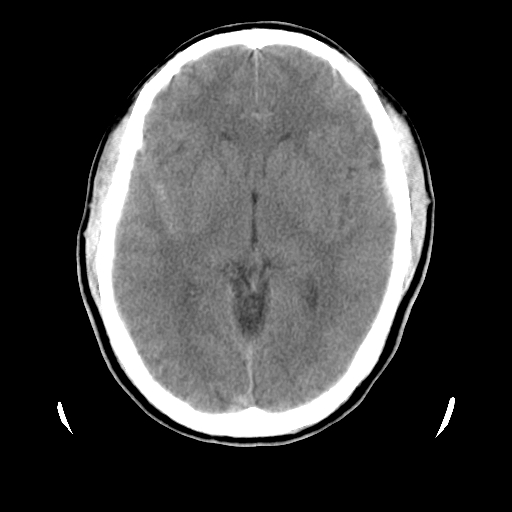

男,51岁,头外伤一小时,呕吐两次。

1)左侧中颅窝蝶骨翼后方硬膜外血肿。2)左侧颞顶部硬膜下血肿。3)蛛网膜下腔出血。4)左侧筛窦及双侧蝶窦炎症(或积血)。5)左侧额部头皮软组织肿胀。